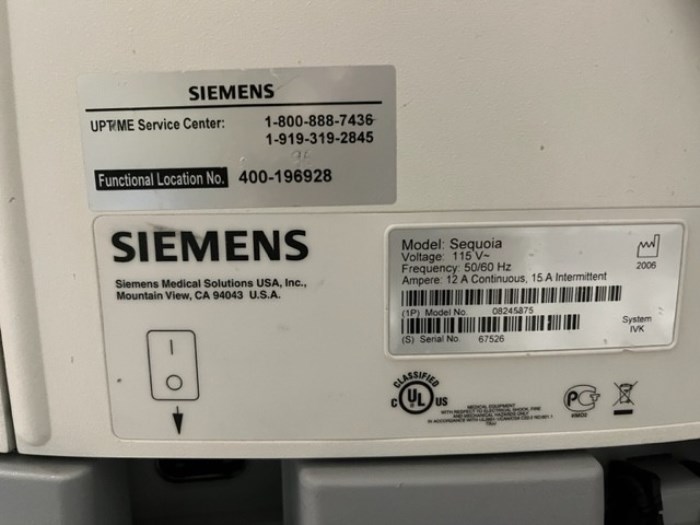

Siemens Sequioa Ultrasound

Pre-owned. In good working condition. Shown as is. Siemens Sequoia Ultrasound. DOM: 2006